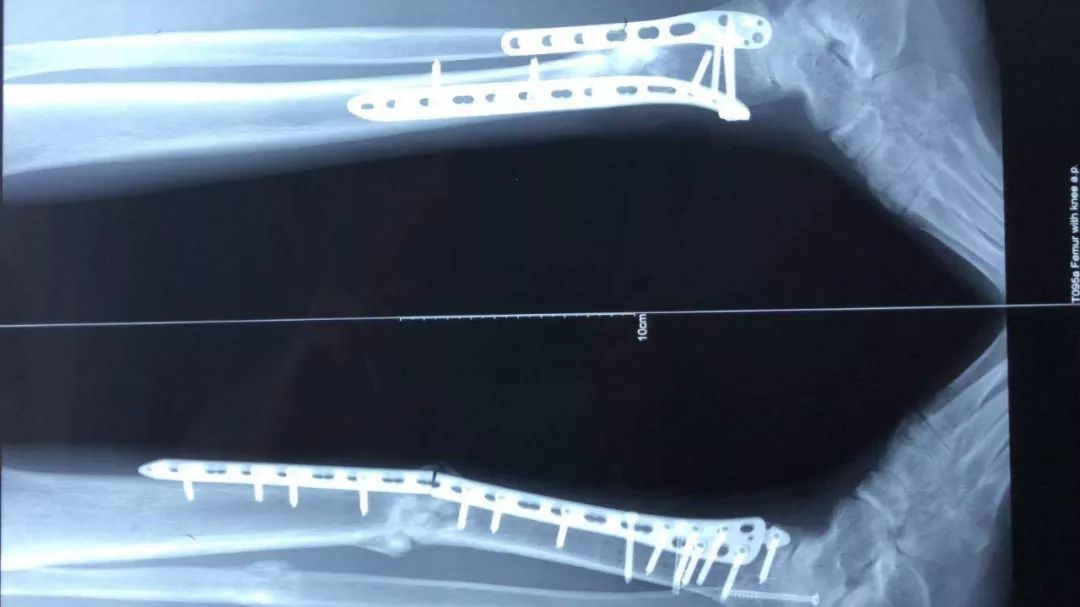

此处应用钢板有两种情况一是不会使用髓内固定,设备条件达不到;再就是理念落后见的病例少,交流少。此处外侧全部是长应力,钢板为张力钢板,内收肌力量强大,目前的钢板不能承受反复的弯曲应力,金属疲劳断裂失败率高,以下病例切开,钢丝捆绑进一步骨膜剥离,破坏了原始血肿,干扰骨愈合,都是失败原因

补救办法:剥削植骨髓内钉固定或动力髁钢板固定。

补救比较好

补救:取下一枚钉子骨折愈合了,关键是取钉子后减少了应力集中,延长了钢板的寿命,骨折愈合了。如果骨不愈合钢板迟早断裂(钢板当初放在内侧会好,蝶形骨块不会坏死,腓骨固定后外侧稳定,内外柱均衡愈合机会增加,当然最好还是髓内钉)。

取下3枚钉子骨折愈合了,与上一例同一位医生所做。张力带钢板,去除3螺钉后,钢板的应力分散,弹性增加,骨折端承受有效的应力刺激,最后骨折愈合。去除螺钉的时候如果加骨皮质剥离重新激发骨愈合会更好。(最好选髓内钉)